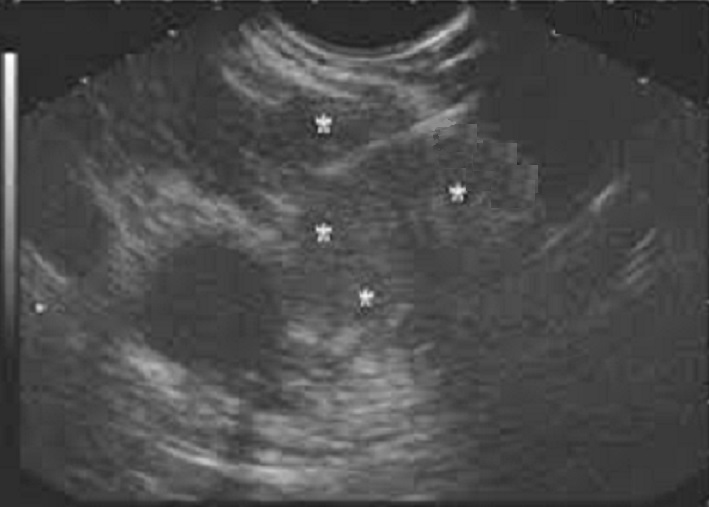

Echographie : Image

echographique d'une cystadenome sereuse est une masse

hypoechogene , contour nette , polylobe situe du corps ( 34%

) du queue ( 26% ) , sa contenue le plus souvant sous forme

de multiple microkyste aechogene , nids d'abeille ou eponge

, cicatrice fibreuse central et calcification central parfoi

se en voyant. Les oligokystes sont se

presenter souvant a la tete du pancreas (40/% ),

uniloculaire macrokystique seul . Endo

echographie et ponction exploratrice presenter sa liquide

est claire et pauvre

en enzymes pancréatiques, en ACE et Ca 19-9